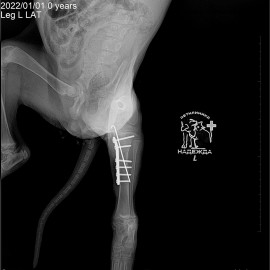

После проведенных исследований был поставлен диагноз: перелом левой голени.

Проведена операция: остеосинтез левой голени.

Снимки 2-3 после операции.